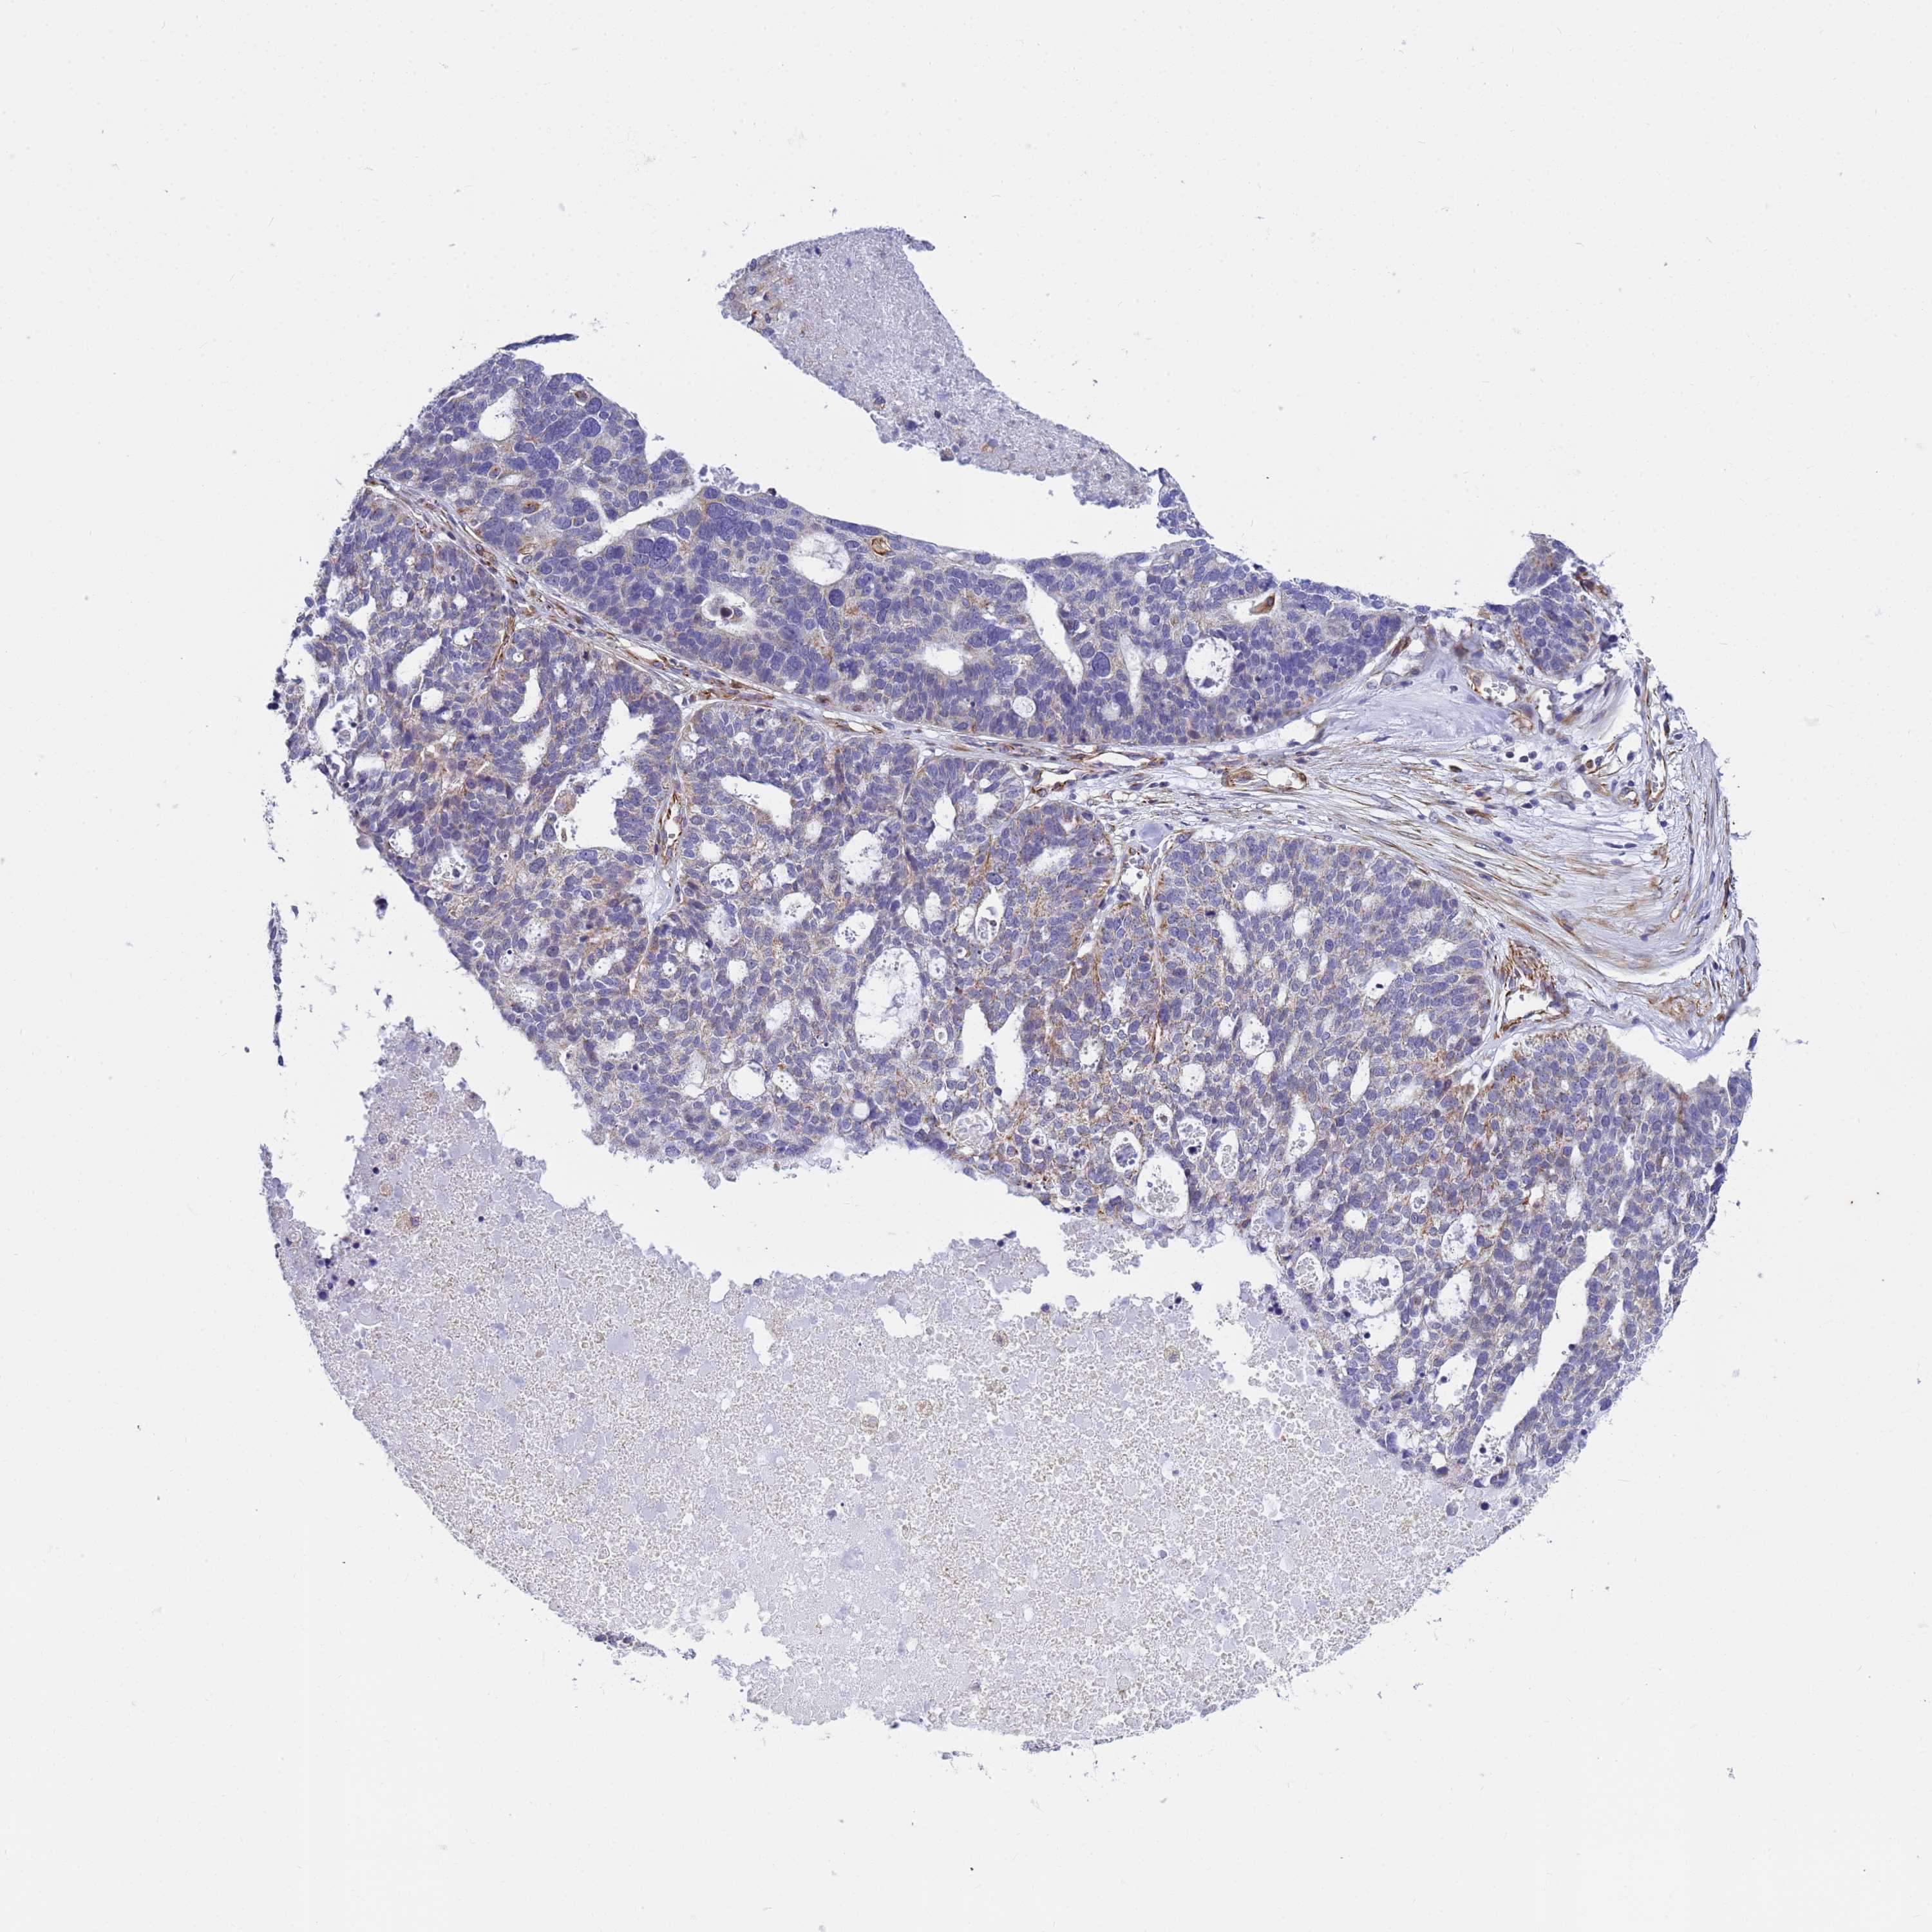

OVARIAN CANCER - Protein expressioni

A mouse-over function shows sample information and annotation data. Click on an image to view it in a full screen mode. Samples can be filtered based on level of antibody staining by selecting one or several of the following categories: high, medium, low and not detected. The assay and annotation is described here.

Note that samples used for immunohistochemistry by the Human Protein Atlas do not correspond to samples in the TCGA dataset.

Antibody stainingi

Antibody staining in the annotated cell types in the current human tissue is reported as not detected, low, medium, or high, based on conventional immunohistochemistry profiling in selected tissues. This score is based on the combination of the staining intensity and fraction of stained cells.

Each image is clickable and will lead to virtual microscopy that enables deeper exploration of all samples and also displays staining intensity scores, fraction scores and subcellular localization as well as patient and tissue information for each sample.

Antibody HPA045278

Staining

High

Medium

Low

Not detected

Intensity

Strong

Moderate

Weak

Negative

Quantity

>75%

75%-25%

<25%

None

Location

Nuclear

Cytoplasmic/membranous

Cytoplasmic/membranous,nuclear

Cystadenocarcinoma, serous, NOS

Carcinoma, endometroid

Cystadenocarcinoma, mucinous, NOS

Carcinoma, NOS